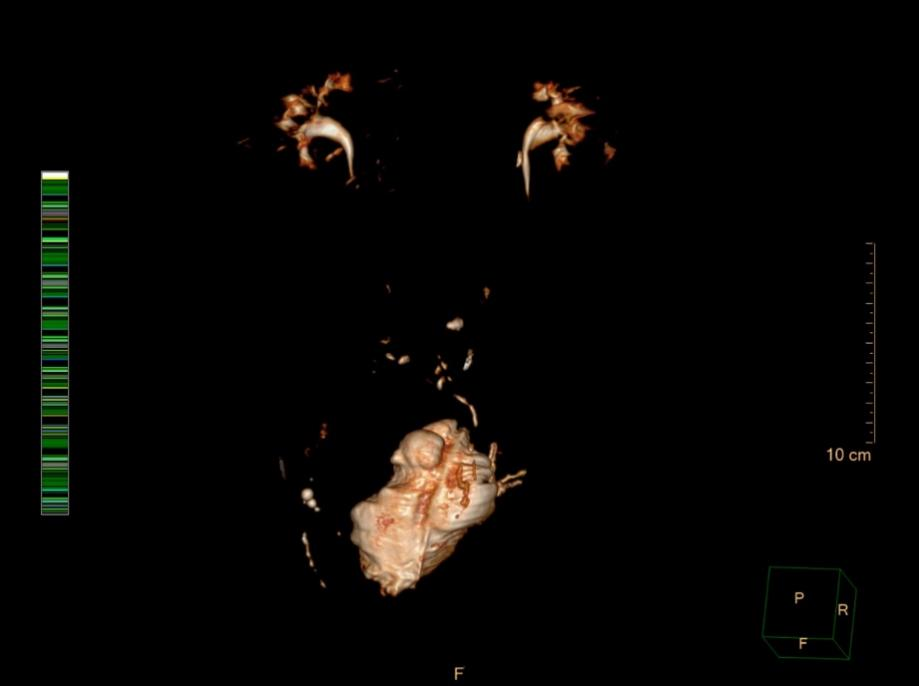

多年来,贵州航天医院各科室紧跟医学前沿,不断强技术、补短板,大力开展新技术、新项目,完成了许多高精尖、高难度、本地区“首例”的技术,填补了医院医疗技术空白,满足了群众日益增长的医疗需求。 本期,我们将为大家带来泌尿外科特色技术——腹腔镜膀胱癌根治术+原位新膀胱术,保留患者自然排尿功能。 案例分享 患者(60岁)在当地医院检查发现膀胱多发肿瘤,在行膀胱肿瘤电切术后,病理提示:高级别尿路上皮癌,该院医生建议患者进行根治性膀胱切除,但切除后肚子上将存在永久造瘘并需佩戴腹壁尿袋,尿液不能自己控制,随时会从肚子流出。 患者拒绝接受挂尿袋的方式,在辗转多个医院咨询后,得知贵州航天医院泌尿外科具有切除膀胱后肚子上不用佩戴尿袋的技术,于是前来我院就诊。泌尿外科腔镜组组长李凯教授带领团队经过反复研究病史及阅片,充分考虑患者需求并征得患者及家属同意后,决定为患者实施腹腔镜根治性膀胱切除术+原位回肠新膀胱术。 CT示膀胱内多发肿瘤 经过6个多小时紧张的手术,顺利切除膀胱并取长约40cm的肠管重新整合成新膀胱,再与输尿管、尿道吻合后原位代替病变的膀胱。切除的组织经过病理检测,提示:恶性上皮肿瘤,符合膀胱高级别浸润性尿路上皮癌,侵及深肌层。 术后3天,患者可以正常排尿;1周后顺利出院;1月后拔出双侧单J管及尿管,患者反馈小便顺畅,无尿失禁等不良情况出现;3月后患者进行尿流率检测,自主排尿通畅。 术后腹壁伤口愈合良好 患者术后3月新膀胱影像 术后3月,患者行尿流率检测 自主排尿通畅 腹腔镜膀胱癌根治术+原位新膀胱术代表了现代泌尿外科技术的最高水平,它不仅为膀胱癌患者提供了根治肿瘤的机会,还通过微创技术和功能重建,帮助患者重获高质量的生活。贵州航天医院泌尿外科李凯教授团队结合患者实际情况对该技术进行了改良,全手工缝合新膀胱,确保患者排尿正常且避免了结石等并发症的出现,已完成多例手术,在遵义地区处于一流水平,为遵义地区患者健康保驾护航。 咨询信息:贵州航天医院便民服务电话 什么是腹腔镜膀胱癌根治术+ 原位新膀胱术 膀胱癌是泌尿系统常见的恶性肿瘤之一,传统的手术方式虽然有效,但创伤大、恢复慢,患者需终生佩戴腹壁尿袋,生活不便且影响社交,给患者带来了极大的身体和心理负担。随着医学技术的不断进步,腹腔镜膀胱癌根治术+原位新膀胱术成为治疗膀胱癌的先进选择,以其精准、微创、恢复快的优势,为患者带来了新的选择和希望。 腹腔镜膀胱癌根治术+原位 新膀胱术原理 腹腔镜膀胱癌根治术是一种微创手术,通过腹腔镜技术,医生可以在高清影像的引导下,精准切除病变的膀胱及周围可能受侵的组织。与传统开腹手术相比,腹腔镜手术切口小、出血少、术后疼痛轻,患者恢复更快。 原位新膀胱术则是在切除膀胱后,利用患者自身的肠道组织(通常为回肠)构建一个新的膀胱,并将其与尿道连接,使患者能够通过正常途径排尿,极大提高了术后生活质量。相比传统的尿流改道术(如回肠代膀胱术),原位新膀胱术更符合生理结构,患者无需佩戴尿袋,生活质量显著提升。 腹腔镜膀胱癌根治术+原位 新膀胱术优势 (一)微创精准,减少创伤 腹腔镜手术通过几个小切口完成操作,避免了传统开腹手术的大切口,减少了术中出血和组织损伤,术后疼痛轻,恢复快。 (二)原位新膀胱,恢复自然排尿功能 原位新膀胱术重建了患者的排尿功能,术后患者可以通过尿道正常排尿,避免了佩戴尿袋的不便和心理压力。 (三)术后并发症少,恢复快 由于手术创伤小,术后感染、肠梗阻等并发症的发生率显著降低,患者住院时间短,能够更快回归正常生活。 (四)提高生活质量 原位新膀胱术不仅保留了患者的排尿功能,还减少了术后对生活的影响,患者可以更好地融入社会和工作。 术后康复与护理 术后患者需遵循医生的指导,逐步恢复饮食和活动。早期可能需要进行膀胱功能训练,以适应新膀胱的排尿功能,定期复查和随访是确保术后长期效果的关键。 友情提醒: 发现无痛性肉眼血尿,需警惕泌尿系肿瘤,尤其是发病率较高的膀胱癌,须尽早就诊。 贵州航天医院泌尿外科专家团队 石 英 泌尿外科主 任 学科带头人 主任医师 中国医师协会泌尿外科分会感染协作组委员,奥林巴斯泌尿系软镜西南区专家组成员,西南地区第一批输尿管软镜专家组成员,贵州省医学会泌尿外科分会委员,贵州省性学会理事,贵州省性学会常务委员,贵州省泌尿外科专业医疗质量控制中心专家委员会委员。 从事泌尿外科专业近30年,熟练掌握泌尿系各类疾病的诊治,具有丰富的临床经验,擅长泌尿系结石、腹膜后肿瘤及泌尿系肿瘤的手术治疗,对泌尿系感染、泌尿系结核、尿源性脓毒血症的救治有独到的见解及抢救经验,在贵州省率先引入输尿管软镜技术,同时在男科领域,对男性阳痿、早泄及前列腺疾病有很深的研究。 李 凯 泌 尿 外 科 副 主 任 医 师 贵州航天医院肿瘤腔镜组带头人,擅长肾癌根治术、输尿管癌根治术、膀胱及前列腺癌根治术、腹腔镜输尿管狭窄切除吻合术、输尿管切开取石术等手术,在遵义市率先开展泌尿系结核后膀胱挛缩全腹腔镜下膀胱扩大术。 贵州省医学会泌尿外科分会青年委员,遵义市医学会男科分会常务委员,遵义市医学会泌尿外科分会常务委员。 李国成 泌 尿 外 科 副 主 任 医 师 中国人体健康科技促进会男科学专业委员会委员,贵州省性学会泌尿外科分会委员,贵州省医学会男科学分会委员,遵义市医学会男科学分会副主任委员兼秘书长,遵义市医学会泌尿外科分会常务委员,贵州航天医院男科带头人。 从事泌尿外科及男科工作10余年,曾多次在上海交通大学附属第一人民医院,中国中医科学院西苑医院进修学习男科;擅长性功能障碍的诊治,男性整形手术,前列腺增生激光手术,显微手术等。 贵州航天医院泌尿外科简介 • ✦ 基本情况 ✦ • 贵州航天医院泌尿外科创建于1968年,经过几代人的努力,微创与内镜手术占比达90%以上。是贵州省临床重点专科建设单位、北京清华长庚医院李建新教授团队诊疗及会诊中心、北京医学会尿路修复与重建诊疗及会诊中心、上海公济泌尿外科集团遵义中心、上海援黔专家李铮教授男科工作室、贵州省泌尿外科质量控制专家委员单位,科室亚专业框架已完善。 • ✦ 专科特色技术 ✦ • (一)泌尿系结石内镜碎石技术 泌尿系结石微创治疗领域方面是贵州省首家引进科医人钬激光碎石技术科室,在遵义地区率先掌握输尿管硬镜、软性镜,经皮肾镜钬激光碎石技术。目前是北京清华长庚医院泌尿外科“手把手”经皮肾镜碎石技术培训基地、贵州省输尿管软镜培训基地。 1.负压吸引可弯曲软镜鞘电子软镜碎石术 2.标准与超微通道相结合的经皮肾镜碎石取石术 (二)微创腹腔镜技术 泌尿外科腹腔镜技术师承于浙江省人民医院、北大、北京解放军总医院。目前采用经腹、经后腹双入路法的腹腔镜技术完成肾部分切除、肾切除、肾输尿管全长切除、肾盂输尿管成形、输尿管狭窄吻合、膀胱翻瓣等手术。在遵义地区率先掌握腹腔镜下膀胱癌根治术、腹腔镜下前列腺癌根治术。 (三)男科、盆底技术临床应用 遵义地区男科分会主委单位,是贵州省首家引进尿动力学检查并取得了全国资质认证科室,也是贵州省首家进行RigiScan检查的单位。在遵义地区率先掌握显微取精子技术以及显微镜下治疗精索静脉曲张、显微镜下输精管吻合、输精管附睾吻合技术。率先采用前列腺激光剜除术治疗前列腺增生症。在陆军军医大学西南医院泌尿外科主任沈文浩教授指导下,完成遵义市首例神经源性膀胱骶神经调节刺激器置入术。 • ✦ 诊疗范围 ✦ • 诊疗范围(除外肾移植、癌栓):泌尿系结石、泌尿系肿瘤、肾上腺疾病、肾积水、前列腺增生、男性生殖器功能障碍(精索静脉曲张、生殖道感染、输精管梗阻等)、盆底功能障碍性疾病(膀胱脱垂、排尿功能异常、尿失禁)、泌尿生殖系畸形。 泌尿外科拥有独立门诊治疗室、日间手术室、尿动力学检查室、精液分析检查室、男性勃起功能检查及治疗室、ESWL治疗室、结石分析检查室。